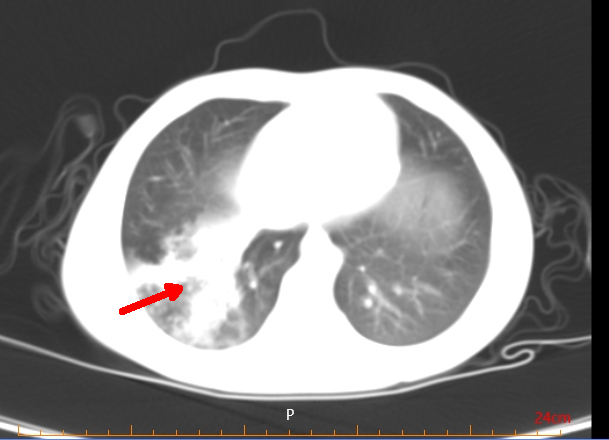

住院医师:主任,您看看这个孩子的片子,这是一个4岁的孩子,病史就3天,高烧加轻微的咳嗽,查了胸部CT显示一侧肺叶全是肺实变。

前面的四种情景,在最近的儿科门诊和病房屡见不鲜。这些患者所得的疾病都是肺炎支原体肺炎。今年的儿童肺炎支原体肺炎来的比往年更猛烈,患病儿童更多,病情更重,很多孩子胸部影像学显示“白肺”,可以说今年是肺炎支原体肺炎“流行大年”。各个医院儿科门诊人满为患,病区床位异常紧张,这使得许多家长非常担心。家长对病毒、细菌可能有一定的了解,面对肺炎支原体可能会比较迷茫。

对于重症肺炎患儿,则需要进一步采取综合措施,包括抗感染、糖皮质激素、支气管镜灌洗、抗凝、丙种球蛋白等联合治疗。当考虑耐药肺炎支原体感染导致重症肺炎时,还会使用到一些可能对儿童牙齿和骨骼产生影响的“非常规”用药,比如四环素类或喹诺酮类药物,但根据已有的治疗经验,短期使用这些药物是安全的。绝大多数重症肺炎支原体肺炎是可以治愈的,但仍有一小部分患儿有发生闭塞性支气管细支气管炎、支气管扩张、肺不张、机化性肺炎等后遗症的可能。